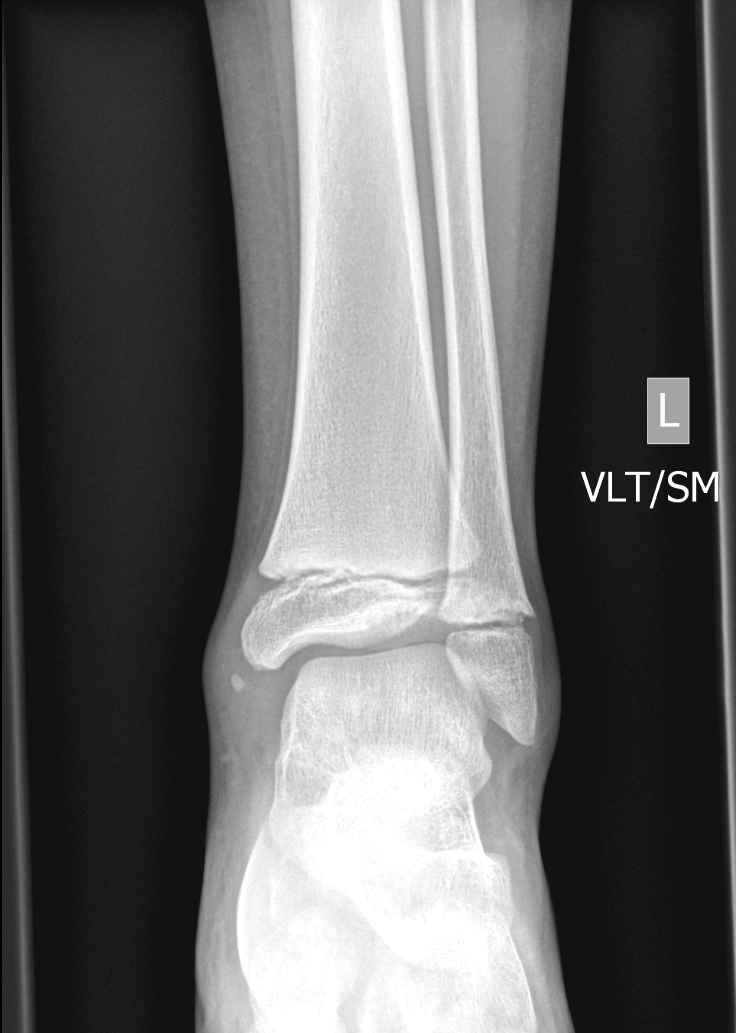

Info Images Findings Impression Reco/Acuity Case Images View Images / Launch Visage Case Notes History 2-month-old presents with decreased right arm movement, increased fussiness, and increased sleepiness for 2 days. Suspected non-accidental trauma. Exam Skeletal survey Prior Study none Dicom View Reference Material

Section 1 Submit Findings CB1550 Findings Skeletal Survey - Technique Check Skull AP/Lat Yes No Cervical and Thoracolumbar spine Yes No Chest X-Ray Yes No Ribs – Left/Right Oblique Yes No Abdominal X-Ray Yes No Pelvis with both hips Yes No Bilateral Humerus, Forearm, Hand Yes No Bilateral Femur, Tibia/fibula, feet Yes No Any additional lateral views of the extremities Yes No The exam is over or under penetrated. Yes No The exam may or may not be limited by overlying structures or soft tissues, body habitus, patient positioning, support devices, or motion. Yes No The area of concern is indicated by the patient, technologist, or care provider. Yes No The area of concern is included on the exam. Yes No Soft Tissues There is soft tissue swelling, indistinctness of fat/muscle planes, gas, or laceration in the area of clinical concern. Yes No There is an effusion, fat pad displacement, or fat fluid level. Yes No There is a radiodense or lucent foreign body. Yes No There are other densities, calcifications, post-surgical changes, or support devices in the soft tissues. Yes No Any support lines/tubes. Yes No Bone There is a break or interruption of the continuity of the cortical or cancellous bone. Yes No There is overriding of the trabeculae with apparent sclerosis. Yes No There is displacement of a fracture fragment. Yes No There is bowing of the bone in addition to the fracture at the apex of the bowed bone concerning for the greenstick. Yes No There is a spiral fracture of the leg concerning for toddler’s fracture. Yes No There is abnormal angulation or bulging of the cortical surface relative to the normal cortex which could be from a buckle or torus fracture. Yes No There is a displaced fragment which may be from avulsion by a tendon, ligament, or joint capsule or from a comminuted or other fracture. Yes No The stress trabeculae or other trabeculae of the cancellous bone are interrupted or otherwise abnormal. Yes No There is subperiosteal or endosteal reaction which could indicate a healing or subacute fracture or other abnormality. Yes No There is hard/soft callus formation. Yes No There is remodeling of the bone. Yes No There is a corner fracture or metaphyseal lesion that could be from nonaccidental trauma. Yes No There are multiple fractures of different ages. Yes No There are vertebral body/spinous process fractures. Yes No There are rib fractures. Location - posterior or lateral. Yes No There is scapular/sternal fracture. Yes No There are fractures of the digits. Yes No There are wormian bones. Yes No There are intrasutural bones. Yes No There is metaphyseal abnormality (lucencies, increased density, erosion) which may be from something other than injury such as stress, metabolic disease (e.g. rickets with loss or distortion of the zone of the provisional calcification), neoplasm (e.g. leukemia), heavy metals, inflammation, or infection. Yes No There are metaphyseal spurs. Yes No There are bony deformities involving multiple bones. Yes No The bones are gracile. Yes No There are non-healing fractures. Yes No There is/are focal or multifocal lytic/lucent, blastic/sclerotic or mixed density lesion(s) or other abnormality. Yes No Overall bone density is increased or decreased with or without thinning or thickening of the cortical or cancellous bone. Yes No Growth plates, ossification centers, apophyses The growth plate(s) is/are abnormal. Yes No There is widening of the physis from a fracture with or without displacement of the epiphysis (Salter-Harris I). Yes No There is a fracture through the physis which then extends into the metaphysis with or without angulation or displacement (S-H II). Yes No There is a fracture through the physis which then extends into the epiphysis and is intra-articular, with or without angulation or displacement (S-H III). Yes No There is a fracture through the metaphysis, physis, and epiphysis which extends into the joint space with or without angulation or displacement (S-H IV). Yes No There is narrowing of the physis from a compression fracture (S-H V). Yes No The apophysis, epicondyle, secondary ossification center, or accessory ossicle is displaced or otherwise abnormal. Yes No The ossification centers are underdeveloped. Yes No Joints and alignment There is an effusion, fat pad displacement, or fat fluid level. Yes No The epiphysis or subchondral bone is fractured, interrupted, flattened, compressed, impacted, displaced, or otherwise abnormal. Yes No There is an intra-articular loose body or chondrocalcinosis. Yes No The joint is widened, narrowed, dislocated, malaligned, or incongruent. Yes No There is pseudoarthrosis. Yes No Other findings There are developmental changes or other anatomic variants or other existing conditions that may or may not be contributing to symptoms which can or should be further evaluated non-emergently or are otherwise incidental. Yes No The remainder of the exam is abnormal for age. Yes No The lungs show focal airspace opacity. Yes No There is pneumothorax. Yes No There is organomegaly. Yes No There is intra-abdominal calcification. Yes No There is displacement of the bowel loops. Yes No There is free intraperitoneal air. Yes No The bowel loops are dilated/obstructed. Yes No There is paraspinal soft tissue abnormality. Yes No